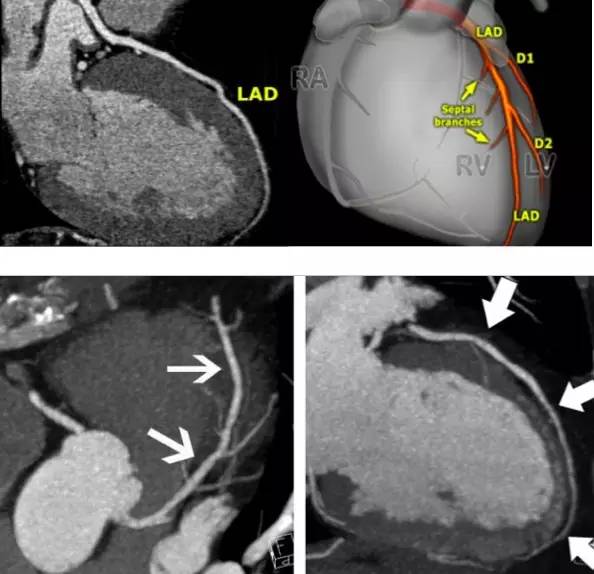

整个做的过程就是静脉注射碘造影剂后,CT机根据造影剂从注射至到达心脏血管不同部位的时间、按照预先设定的程序快速进行扫描成像,这个成像是把一支血管一个层面一个层面扫描出来的,也就相当于把一根血管截成一小段一小段成像,然后用计算机技术把这些影像重新组合(重建)起来,就可以看血管了。所以这个造影看到的图像,跟插导管造影看到的图像有所不同。

第四,对诊断心肌桥有帮助。因为CT检查可以同时看血管和旁边的心肌,所以对心肌桥的诊断要更好一些。